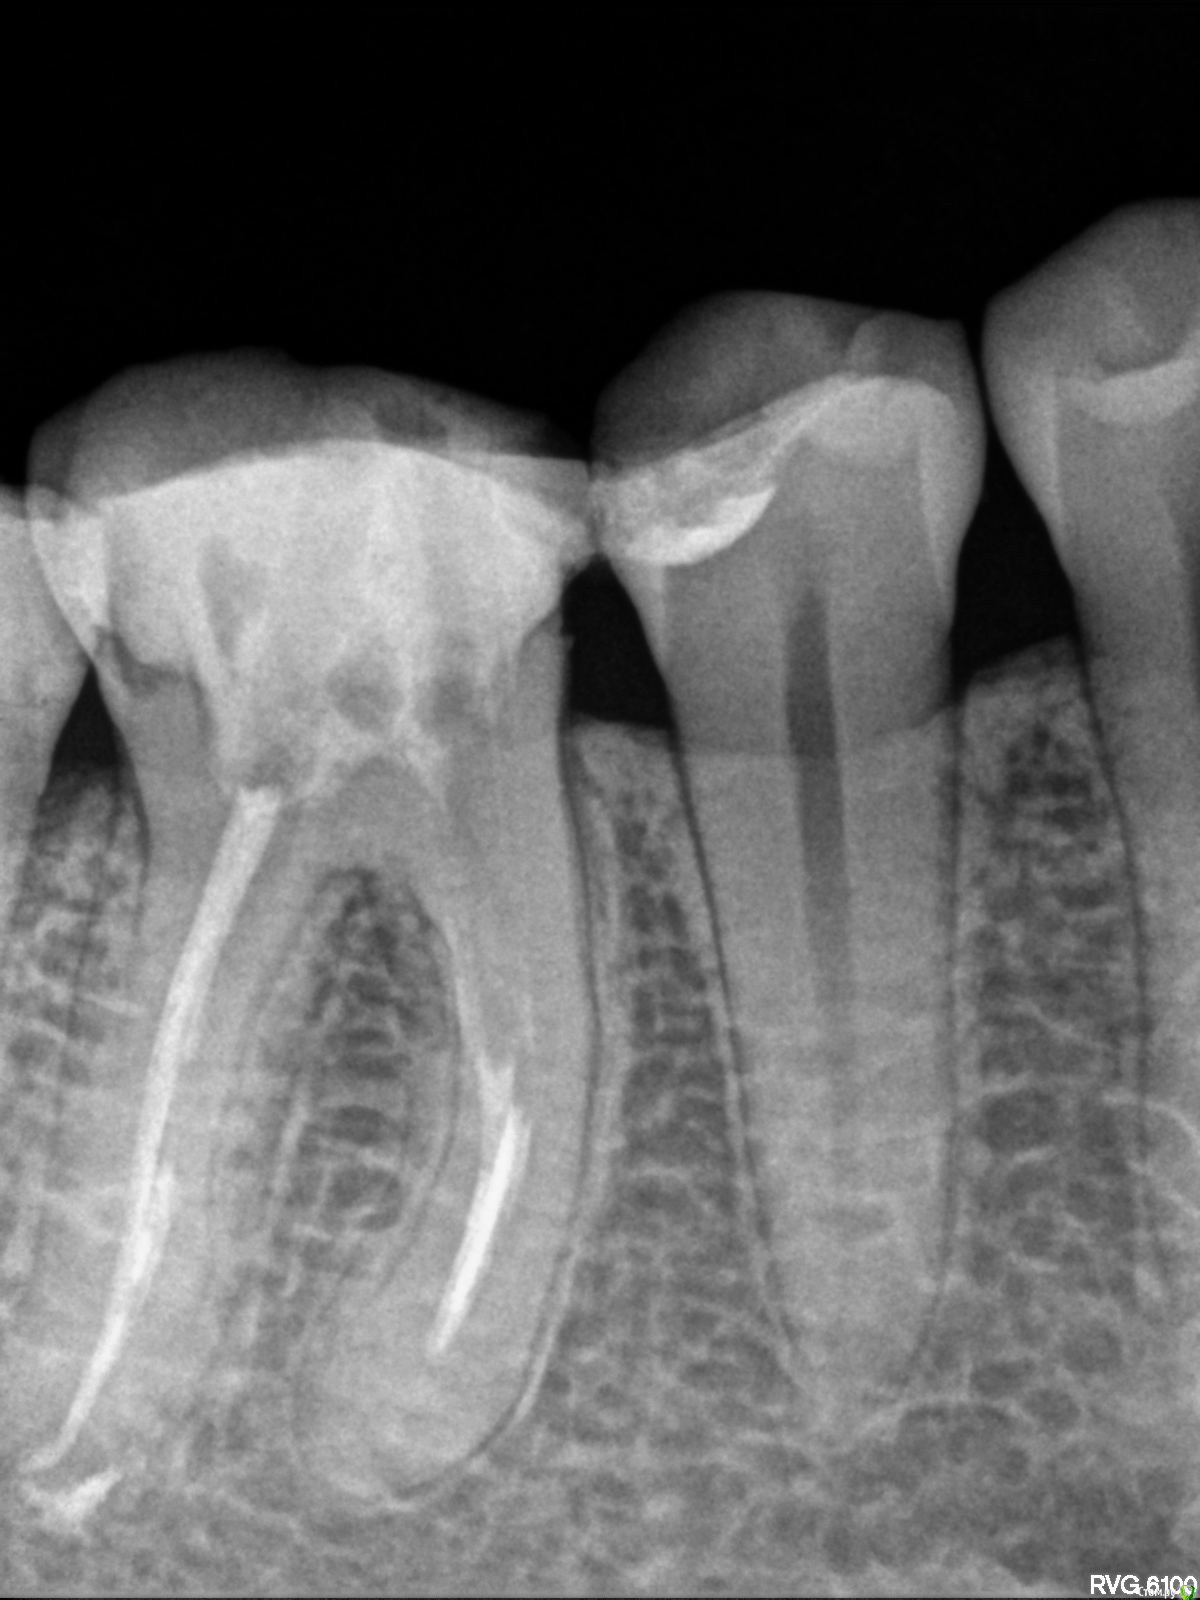

ann_bell Опубликовано 18 ноября, 2015 Поделиться Опубликовано 18 ноября, 2015 (изменено) Здравствуйте! Нужен совет. Нижняя шестерка пролечена 3 года назад, каналы запломбированы. Неделю назад откололась задняя стенка зуба. На приеме стоматолог посоветовала удалять, т.к. стенка откололась слишком глубоко. Хотя по снимку корни в порядке, никаких патологий нет.Врач сказала, что в принципе корень можно сохранить и установить коронку, но это будет дорого (перелечивание каналов 20000 + коронка с вкладкой) и конструкция будет очень ненадежной, придется постоянно подклеивать коронку. И сама врач за эту работу не возьмется, потому что вариант, мол, проигрышный изначально. Мост не хочу однозначно. Удалять и ставить имплант или попытаться сохранить коронкой? Шанс спасти все-таки есть, даже стоматолог это признала. Нужно ли его использовать?Снимок, к сожалению, остался у врача. На зуб поставили временную пломбу. Изменено 18 ноября, 2015 пользователем ann_bell Ссылка на комментарий

ann_bell Опубликовано 20 ноября, 2015 Автор Поделиться Опубликовано 20 ноября, 2015 Выкладываю снимок Ссылка на комментарий

IvanK Опубликовано 21 ноября, 2015 Поделиться Опубликовано 21 ноября, 2015 Если зуб разрушен ниже уровня десны , то я бы удалил 2 Ссылка на комментарий